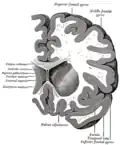

Transverse cut of brain (horizontal section), basal ganglia is blue | |

Structure

Along with the putamen, the caudate forms the dorsal striatum, which is considered a single functional structure; anatomically, it is separated by a large white-matter tract, the internal capsule, so it is sometimes also described as two structures—the medial dorsal striatum (the caudate) and the lateral dorsal striatum (the putamen). In this vein, the two are functionally distinct not because of structural differences, but merely because of the topographical distribution of function.

The caudate nuclei are near the center of the brain, sitting astride the thalamus. There is a caudate nucleus in each hemisphere of the brain. Each nucleus is C-shaped, with a wider "head" (caput in Latin) at the front, tapering to a "body" (corpus) and a "tail" (cauda). Sometimes a part of the caudate nucleus is called the "knee" (genu).[6] The caudate head receives its blood supply from the lenticulostriate artery; the tail of the caudate receives its blood supply from the anterior choroidal artery.[7]

The head and body of the caudate nucleus form part of the floor of the anterior horn of the lateral ventricle. The body travels briefly towards the back of the head; the tail then curves back toward the anterior, forming the roof of the inferior horn of the lateral ventricle. This means that a coronal section (on a plane parallel to the face) that cuts through the tail will also cross the body and head of the caudate nucleus.